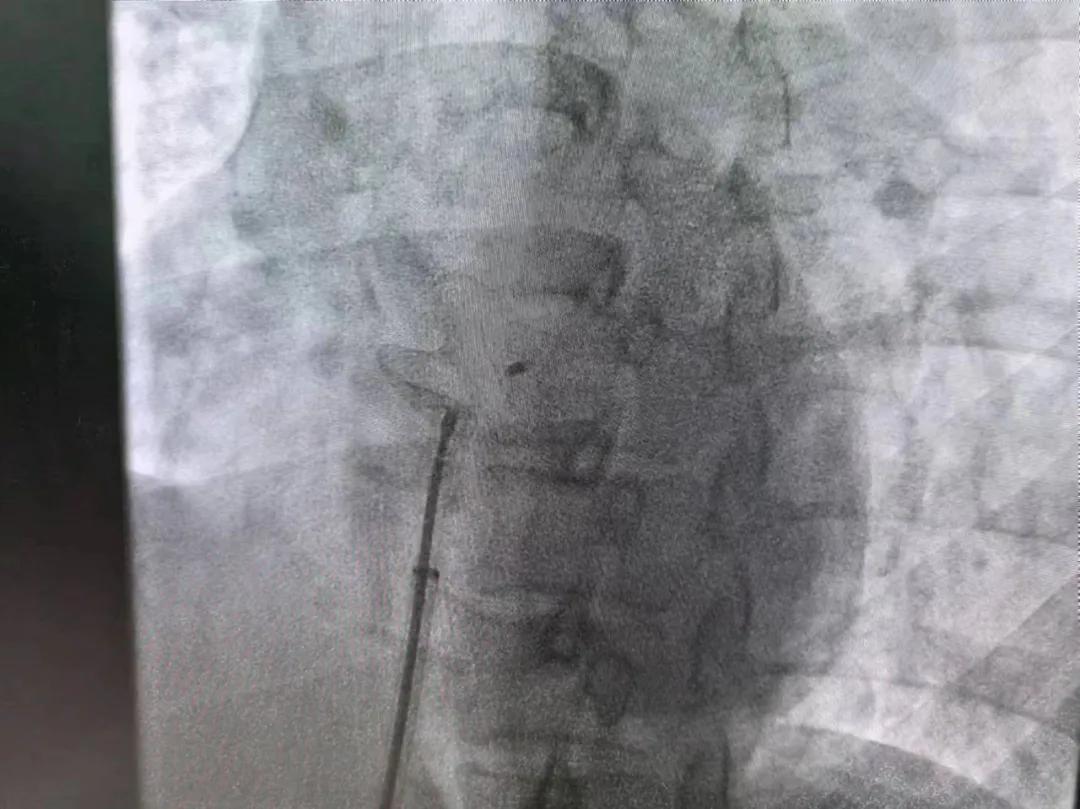

繼3月14日市二院成功開展首例卵圓孔未閉介入封堵術(shù)之后,3月21日上午,市二院院長王瑾及心血管內(nèi)科主任李慧新帶領(lǐng)心血管內(nèi)科介入團(tuán)隊(duì),再次成功為患者實(shí)施“經(jīng)皮房間隔缺損封堵術(shù)”,手術(shù)過程順利。該例病人的成功手術(shù)及康復(fù),標(biāo)志著市二院心血管內(nèi)科在結(jié)構(gòu)性心臟病介入診療中再次達(dá)到了新高度。

患者為中年女性,41歲,近2年一直反復(fù)出現(xiàn)頭暈、頭痛,曾先后在多家醫(yī)院就診。近期患者癥狀加重,出現(xiàn)活動后氣喘合并胸悶癥狀,來到心血管內(nèi)科就診。經(jīng)心臟彩超檢查顯示:患者房間隔下段連續(xù)性中斷,缺損直徑達(dá)到了13mm,肺動脈壓已經(jīng)輕度增高,確診為房間隔缺損。

于是,院長王瑾會診后,詳細(xì)詢問患者病史,認(rèn)真分析臨床癥候群并準(zhǔn)確診斷,耐心做好患者及家屬病情告知和充分溝通。經(jīng)過完善的術(shù)前評估及準(zhǔn)備,心血管內(nèi)科介入團(tuán)隊(duì)成功為患者實(shí)施“經(jīng)皮房間隔缺損封堵術(shù)”,手術(shù)過程順利。近日,患者已順利康復(fù)出院。 (尹紅婭 潘長林)